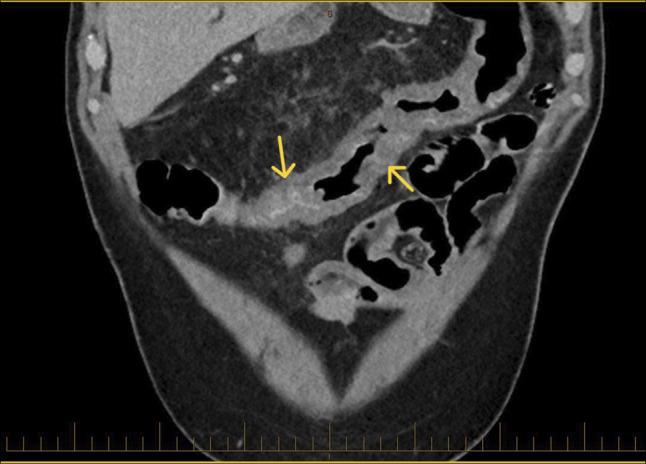

由于特发性结肠静脉曲张(ICV)引起的下消化道出血是非常罕见的。我们报告一位66岁男性复发性尿血,但没有肝脏疾病或门静脉高压症病史。结肠镜检查显示整个结肠有广泛的静脉曲张。没有生化或放射学证据表明肝硬化或门静脉高压症。ICV的潜在病因尚不清楚,在没有标准化治疗方案的情况下,这种疾病的管理具有挑战性。非选择性β受体阻滞剂可以考虑,尽管未知的ICV病理生理和他们的作用在这个临床实体。在我们的病例中,成功的管理包括立即内窥镜治疗和卡维地洛的二级预防。

Lower gastrointestinal bleeding due to idiopathic colonic varices (ICV) is very rare. We present a 66-year-old man with recurrent hematochezia but without history of liver disease or portal hypertension. Colonoscopy revealed extensive varices throughout the colon. There was no biochemical or radiological evidence of cirrhosis or portal hypertension. The underlying etiology of ICV is unknown, and management of this condition is challenging without standardized treatment protocols. Nonselective beta-blockers could be considered despite the unknown ICV pathophysiology and their effect in this clinical entity. The successful management in our case included immediate endoscopic treatment and secondary prophylaxis with carvedilol.